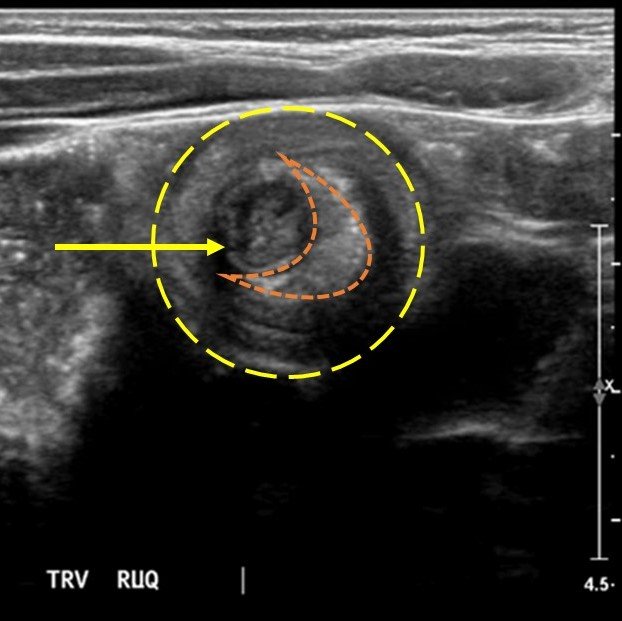

Significant findings:

The patient’s abdominal ultrasound revealed intussusception in the right upper abdominal quadrant. The transverse ultrasound view showed a “doughnut sign” (dashed yellow line), telescoping bowel (yellow arrow), and invaginated hyperechoic mesenteric fat with crescent configuration (dashed orange line). The sagittal ultrasound view demonstrated the intussusception formed by the outer recipient bowel loop (yellow arrows), invaginated hyperechoic mesenteric fat (orange asterisks), and telescoping bowel centrally (red arrow).